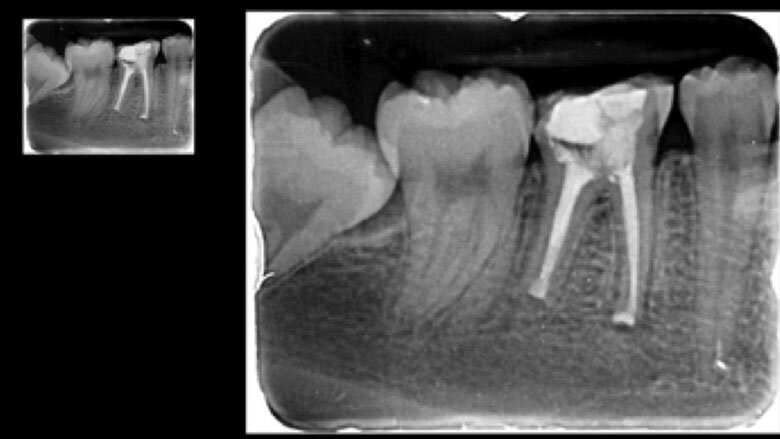

Apicectomía del diente 46.

El reimplante intencional consiste en extraer el diente de manera atraumática, fuera de boca examinar la causa que produce la infección, y volverlo a reimplantar en el menor tiempo posible.

El reimplante intencional consiste en extraer el diente de manera atraumática, y entonces fuera de boca examinar la causa que produce la infección, y volverlo a reimplantar en el menor tiempo posible.

La manipulación de instrumentos microquirúrgicos y ultrasonidos es más fácil con el diente fuera de la boca.

Se debe proteger al máximo la integridad de las células del ligamento periodontal, para que se dé una buena cicatrización de las mismas durante la reimplantación. La manera de protegerlas es usar un tiempo extraoral extra corto, no mayor a 15 minutos y entre más bajo mejor. Después de la extracción del diente, las raíces se examinan en busca de fracturas, conductos adicionales o istmo y cualquier característica anatómica adicional que requiera sellarse para evitar la salida de bacterias al exterior. La inspección de la raíz se realiza mejor con la ayuda de un microscopio dental6. Dado que no se necesita una osteotomía, la reimplantación no produce la pérdida de hueso vestibular o palatino para llegar al ápice radicular. Esto facilita la curación postoperatoria al no sacrificar hueso sano para llegar al sitio donde se ubica el ápice radicular. Durante la apicectomía convencional, el campo de visión está limitado por la osteotomía y las estructuras adyacentes, como el arco cigomático y el tejido de la mejilla. Sostener un diente extraído permite un acceso total para inspeccionar toda la superficie de la raíz (4). La manipulación de instrumentos microquirúrgicos y ultrasonidos es más fácil con el diente fuera de la boca. Una reducción del tiempo extra oral es imprescindible en la prevención de la anquilosis, la reabsorción radicular y para promover el proceso de curación peri-radicular mediante la prevención del daño y deshidratación de las células periodontales7. Es grandioso darse cuenta cómo los pacientes quedan altamente agradecidos por conservar sus dientes. Es el endodoncista o el odontólogo el que decide desahuciar dientes que pueden salvarse, y si como especialistas nos entrenamos en técnicas avanzadas, más dientes podremos salvar de la pérdida. En muchos casos, factores económicos impiden que un paciente que pierde los dientes, pueda reemplazarlos, y la falta de dientes está relacionado con problemas gastrointestinales, con cáncer de estomago, cáncer colon rectal e inclusive con Alzheimer8.9. Debemos de verdad aumentar el valor que le damos a los dientes naturales; si fuéramos a perder un riñón, ¿no agotaríamos todos los recursos por salvarlo? Nuestra meta debe ser lograr que nuestros pacientes lleguen con sus dientes naturales hasta la vejez.